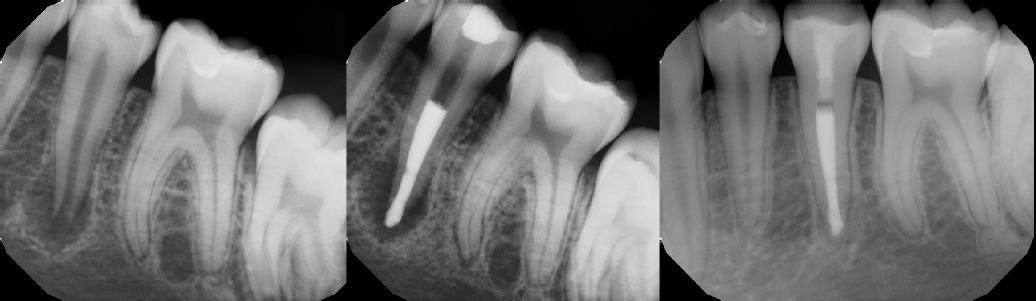

COMPLICATED ANATOMY LARGE LESIONS CALCIFIED CANALS PERFORATION / RESORPTION SEPARATED INSTRUMENTS SURGICAL CASES RETREATMENT / pOST REMOVAL OPEN APICES ACCESS THRU CROWNS Root Canal Case Portfolio

Pre-op Post-op 6 mos.